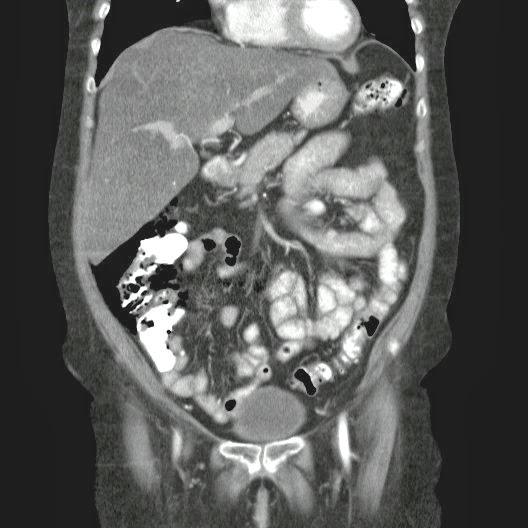

Caso Interesante #4

Adulto masculino, 1 semana de fiebre y malestar general.

¿Dónde esta ubicado el hallazgo?